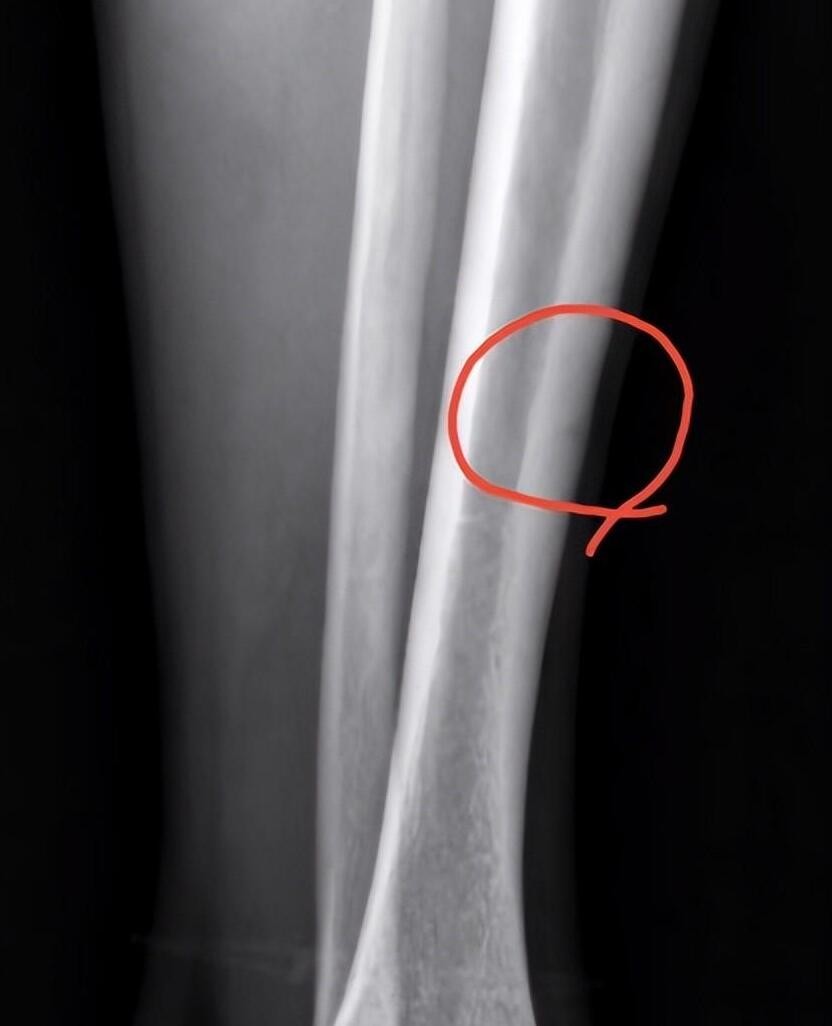

热点事件:广厦男篮核心球员孙铭徽近期在社交媒体上披露自己左脚胫骨受损的影像记录以及治疗情形。尽管未明确病因及病情严重程度,然而从其积极向外传达的信息和乐观的表现来看,该伤势尚处于可控范畴,预期将会较快恢复。

广厦队所面临的伤病问题较为严重,由于他们是夺冠大热队伍,重要球员的缺席将对战局带来重大影响。针对核心队员孙铭徽的康复进展,依然存在不确定性。即使他能在季后赛出战,也需充足的时间来调整到最佳状态。